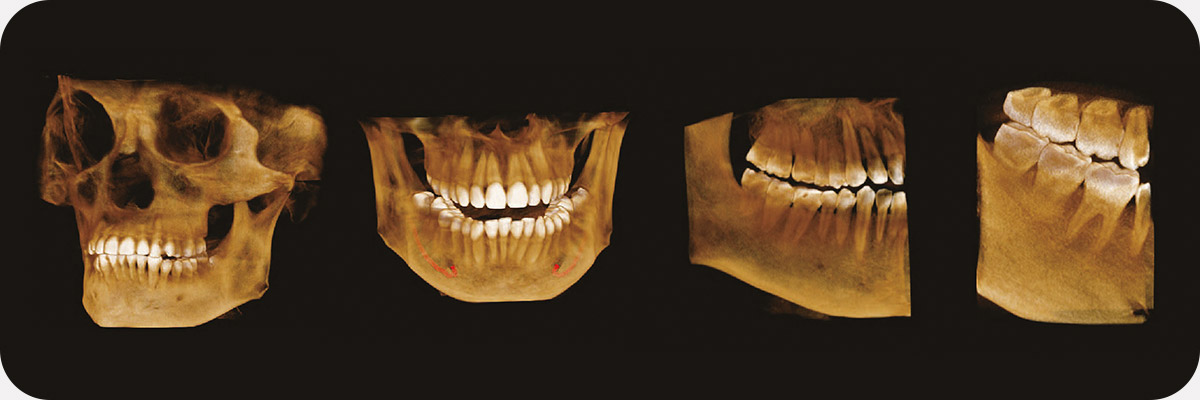

Пример 3D исследования дентального компьютерного 3D томографа Volux 55 Genoray.jpg